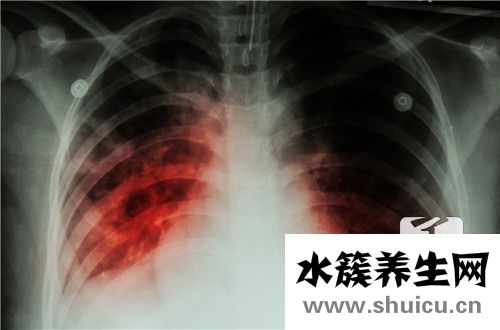

肺是非常重要的人體器官。 它可以包含通風(fēng),吸入,調(diào)節(jié)吸入,還可以促進(jìn)肺部血液循環(huán)系統(tǒng)。 當(dāng)您感覺(jué)略微呼吸不暢,并且肺部感到不適時(shí),大多數(shù)人選擇去醫(yī)院的門診進(jìn)行檢查。 如果他們被診斷出肺密度低和...